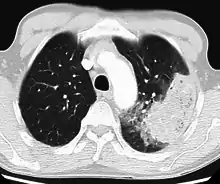

A chest radiograph is frequently used in diagnosis.[22] In people with mild disease, imaging is needed only in those with potential complications, those not having improved with treatment, or those in which the cause is uncertain.[22][61] If a person is sufficiently sick to require hospitalization, a chest radiograph is recommended.[61] Findings do not always match the severity of disease and do not reliably separate between bacterial and viral infection.[22]

X-ray presentations of pneumonia may be classified as lobar pneumonia, bronchopneumonia, lobular pneumonia, and interstitial pneumonia.[66] Bacterial, community-acquired pneumonia classically show lung consolidation of one lung segmental lobe, which is known as lobar pneumonia.[35] However, findings may vary, and other patterns are common in other types of pneumonia.[35] Aspiration pneumonia may present with bilateral opacities primarily in the bases of the lungs and on the right side.[35] Radiographs of viral pneumonia may appear normal, appear hyper-inflated, have bilateral patchy areas, or present similar to bacterial pneumonia with lobar consolidation.[35] Radiologic findings may not be present in the early stages of the disease, especially in the presence of dehydration, or may be difficult to interpret in the obese or those with a history of lung disease.[23] Complications such as pleural effusion may also be found on chest radiographs. Laterolateral chest radiographs can increase the diagnostic accuracy of lung consolidation and pleural effusion.[34]

A CT scan can give additional information in indeterminate cases.[35] CT scans can also provide more details in those with an unclear chest radiograph (for example occult pneumonia in chronic obstructive pulmonary disease) and can exclude pulmonary embolism and fungal pneumonia and detect lung abscess in those who are not responding to treatments.[34] However, CT scans are more expensive, have a higher dose of radiation, and cannot be done at bedside.[34]